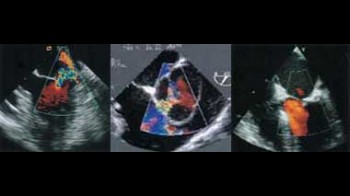

- transtorakalnu ehokardiografiju